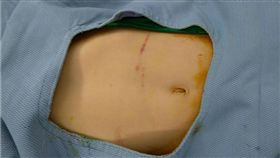

婦罹癌腫瘤卡食道 醫用她的大腸成功重建

南投一名年約60歲的陳姓婦人,平時生活簡單也不菸不酒...